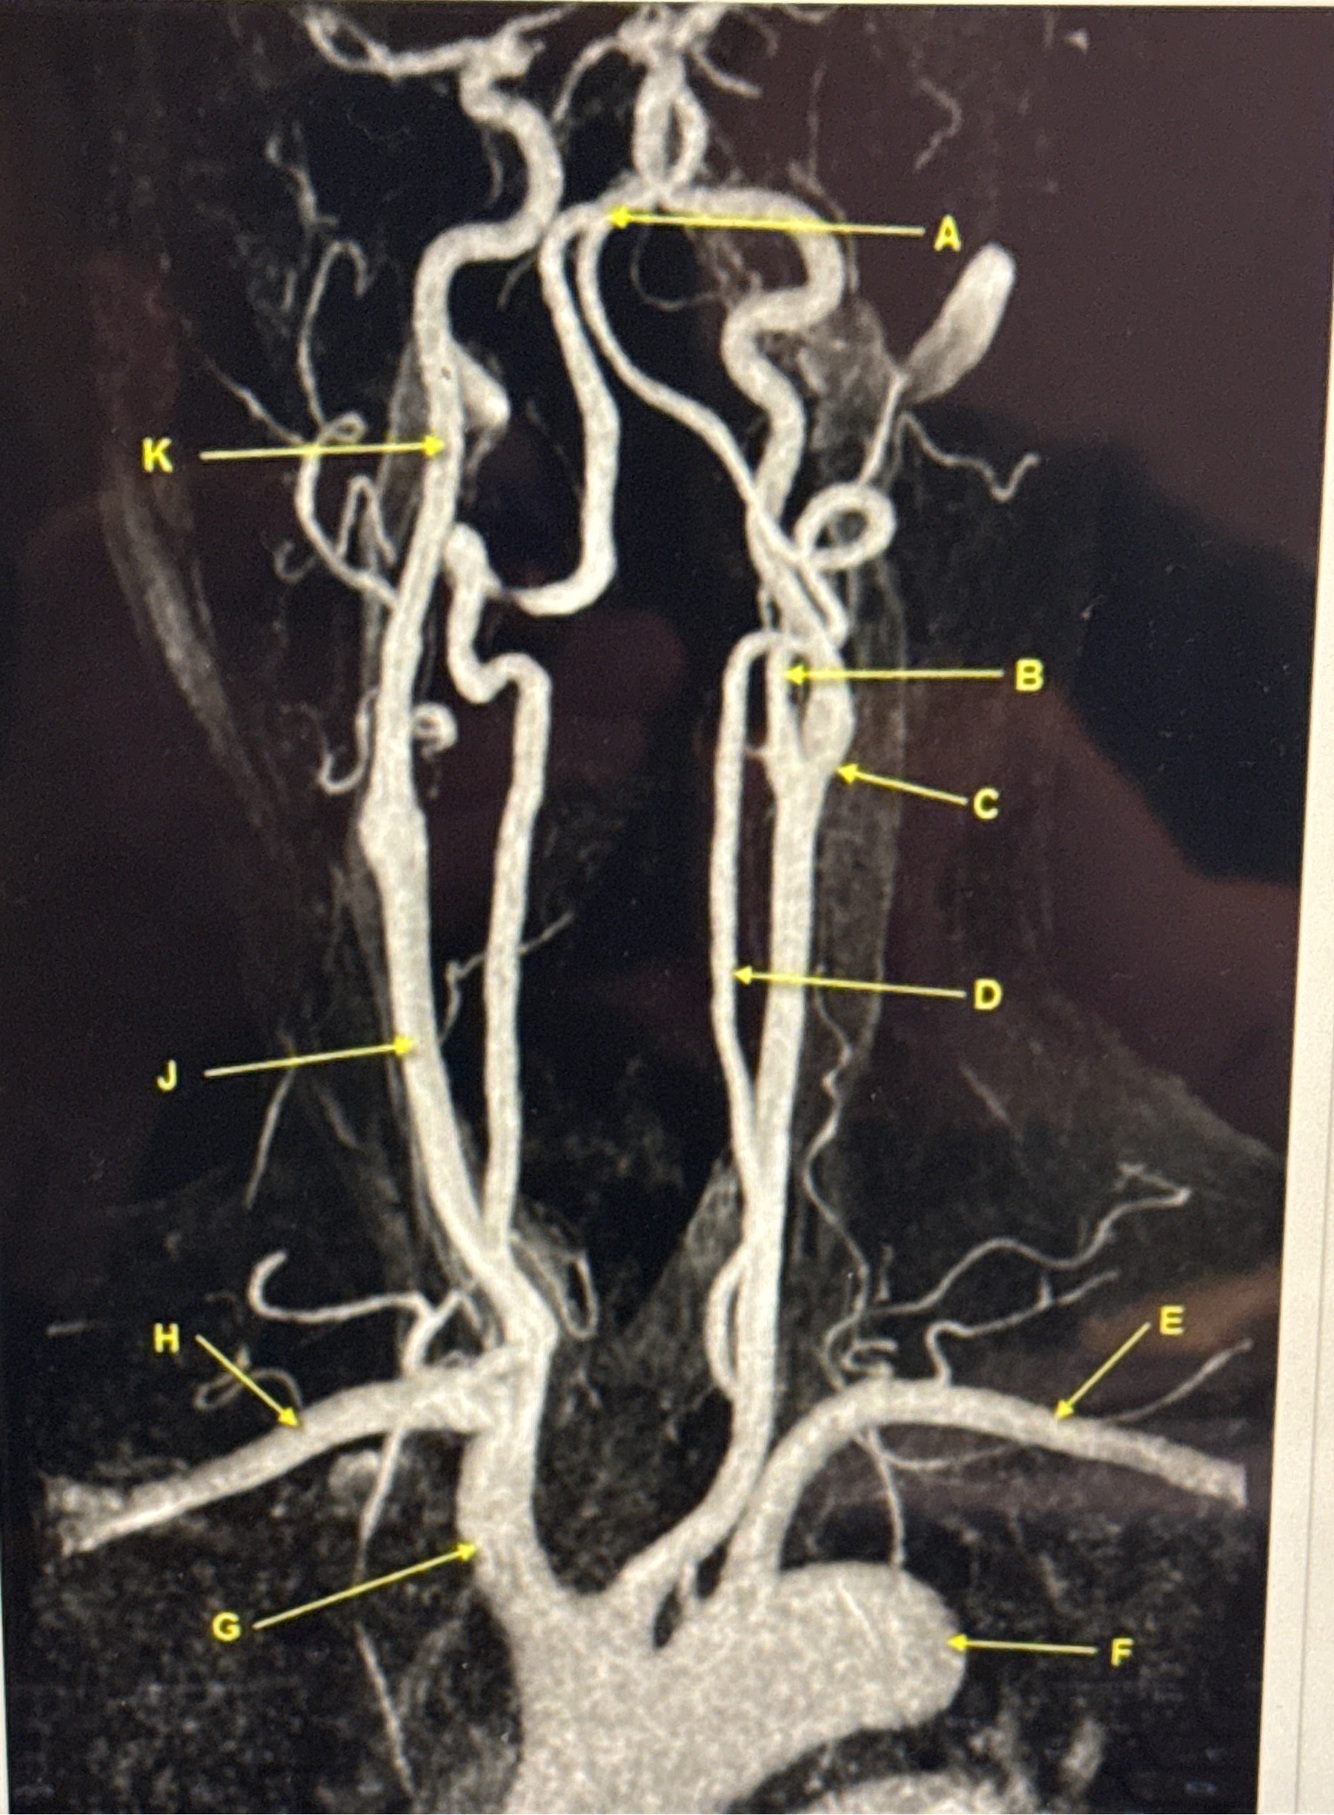

Q

What kind of MR image

A

MRA EXTRACRANIAL CIRCULATION

Letter B points to

Letter J points to

Letter A points to the

Letter E points to the

Letter K points to the

Letter C points to the

Letter B points to the _______ and letter D points to the ______

B. External carotid artery

D. Vertebral artery

Letter E points to the _____ and letter F points to the _____

E. Left subclavian artery

F. Thoracic aorta

Letter G points to the _____ , letter H points to ______ and letter J points to the

G. Brachiocephalic

H. Right subclavian artery

J. Common carotid artery

Letter K points to the ________,

K. Internal carotid artery